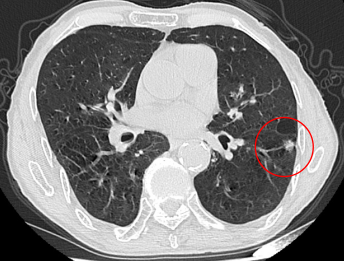

患者吳爺爺,90歲,胸部增強CT提示左肺高危肺結節,肺癌可能性極大。因患者高齡、肺功能較差,不能耐受外科手術,患者及家屬對肺部高危結節非常擔心。

左肺結節